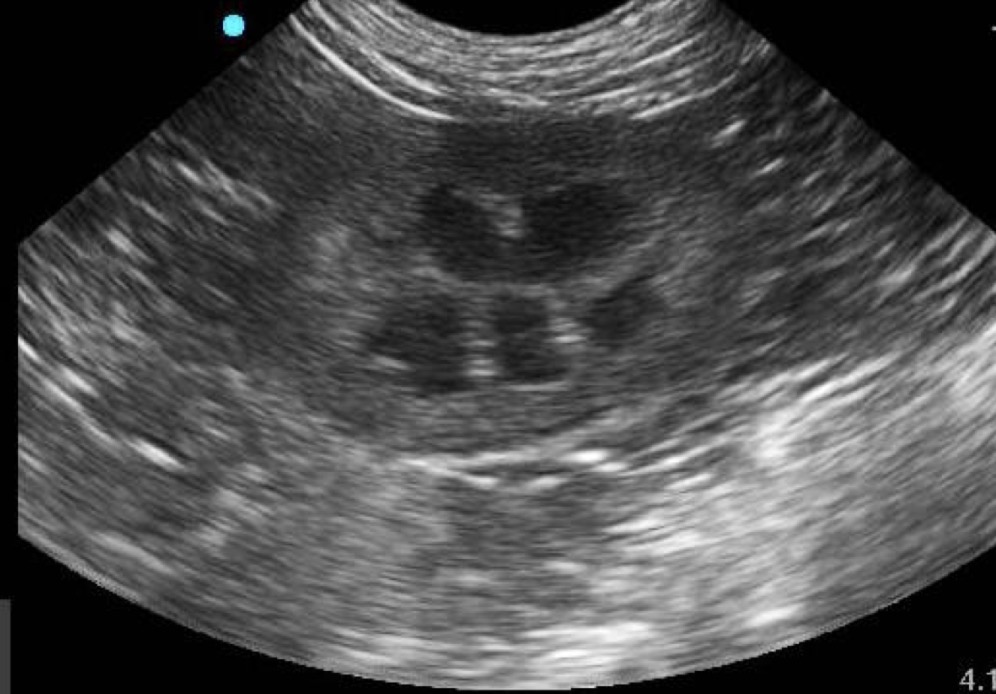

Kidney

What organ is prominent in this ultrasound?

Hyper-echoic cortex and medullary rim sign

What anomalies are occurring in this kidney